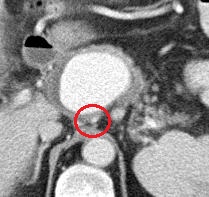

术前CT

胃左动脉起自肝左

动脉瘤的顶

动脉瘤的底

胃左动脉(动脉瘤底) 胃左动脉

胃左动脉 胃左动脉(动脉瘤顶)